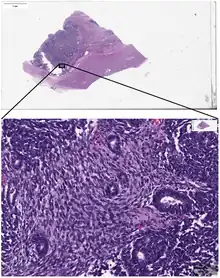

_stain_of_mixed_malignant_germ_cell_tumor_-_crop.png.webp)

Digital pathology has been approved by the FDA for primary diagnosis.[9] The approval was based on a multi-center study of 1,992 cases in which whole-slide imaging (WSI) was shown to be non-inferior to microscopy across a wide range of surgical pathology specimens, sample types and stains.[10] While there are advantages to WSI when creating digital data from glass slides, when it comes to real-time telepathology applications, WSI is not a strong choice for discussion and collaboration between multiple remote pathologists.[11] Furthermore, unlike digital radiology where the elimination of film made return on investment (ROI) clear, the ROI on digital pathology equipment is less obvious. The strongest ROI justification includes improved quality of healthcare, increased efficiency for pathologists, and reduced costs in handling glass slides.[12]

- Figure 2 - available via license: Creative Commons Attribution 4.0 International - ↑ "FDA allows marketing of first whole slide imaging system for digital pathology" (Press release). FDA. April 12, 2017. Retrieved May 24, 2017.